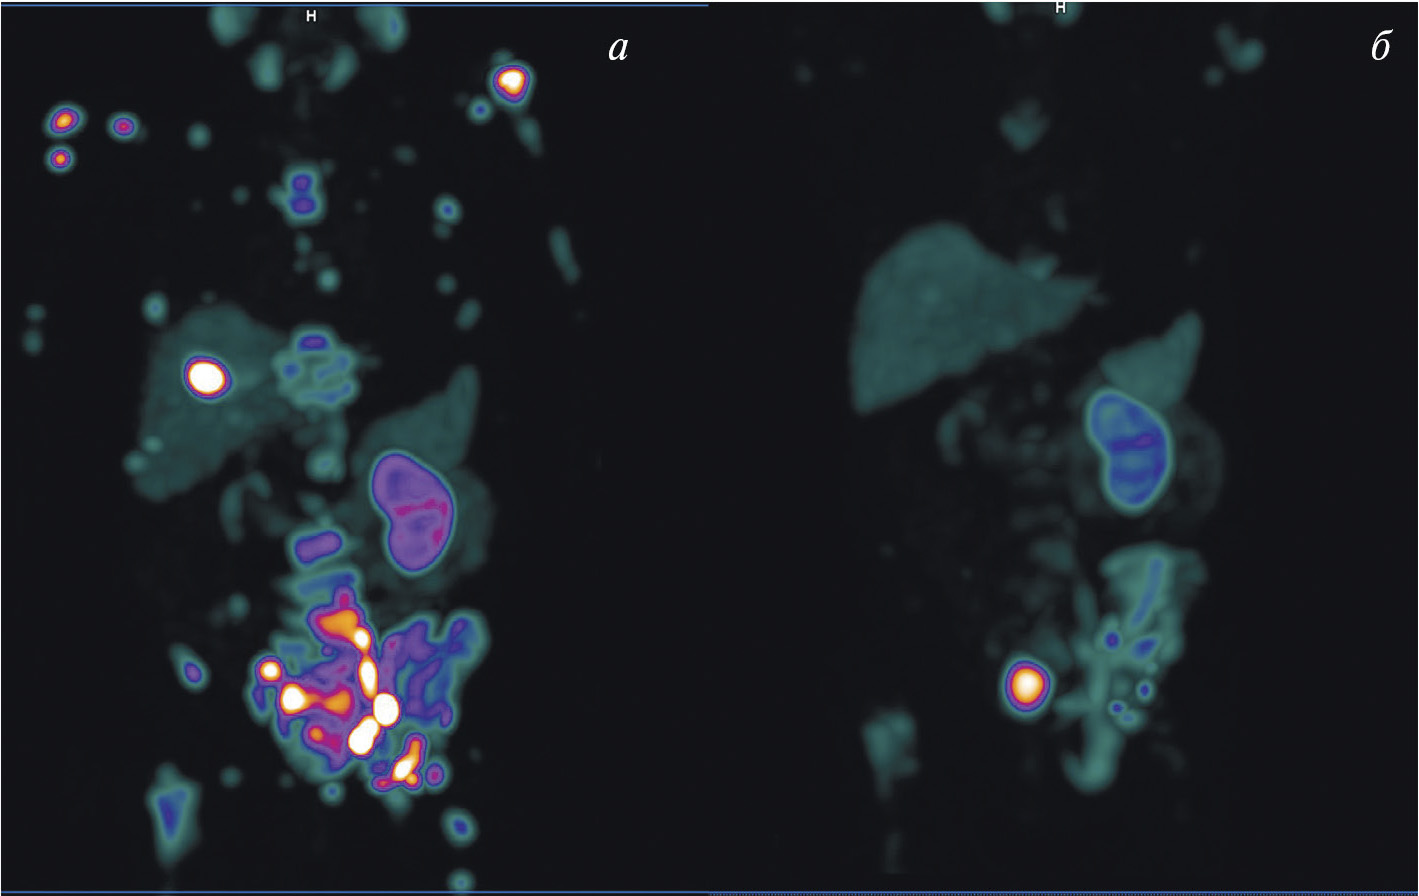

В мировой ядерной медицине для сцинтиграфии обычно применяют 111In-пентетреотид, или 111In-октреотид ([111In-DTPA]octreotide, OctreoScan, Tyco Healthcare, США; АО “Фармсинтез”, Россия). Основные показания к его использованию — стадирование, рестадирование и мониторинг лечения нейроэндокринных SSTR-позитивных опухолей. В последние годы 111In-пентетреотид служит для радионавигации при хирургическом лечении новообразований с гиперэкспрессией соматостатиновых рецепторов. К сожалению, физические характеристики индия-111 (длительный период полураспада, неоптимальный для регистрации на гамма-камере спектр излучения, высокая стоимость циклотронного производства) ограничивают его применение в радионуклидной диагностике. В связи с этим не подвергается сомнению актуальность создания в России меченного технецием-99м октреотида для ОФЭКТ-диагностики нейроэндокринных опухолей. Разработкой такого радиофармпрепарата в рамках проекта федеральной целевой программы “Фарма-2020” занимался ТПУ в сотрудничестве с НИИ онкологии Томского НИМЦ. Клинические испытания отечественного 99mТс-октреотида продемонстрировали его высокую эффективность при диагностике и стадировании НЭО (рис. 3). В настоящее время набор для приготовления этого РФЛП зарегистрирован в России под названием “Нейроскан, 99mТс”, а его производство налажено в ТПУ.

Рис. 3. ОФЭКТ/КТ с 99mТс-октреотидом пациента с нейроэндокринным раком лёгкого: а — конгломерат первичной опухоли и метастазов в лимфатические узлы; б — метастазы в кости; в – селезёнка